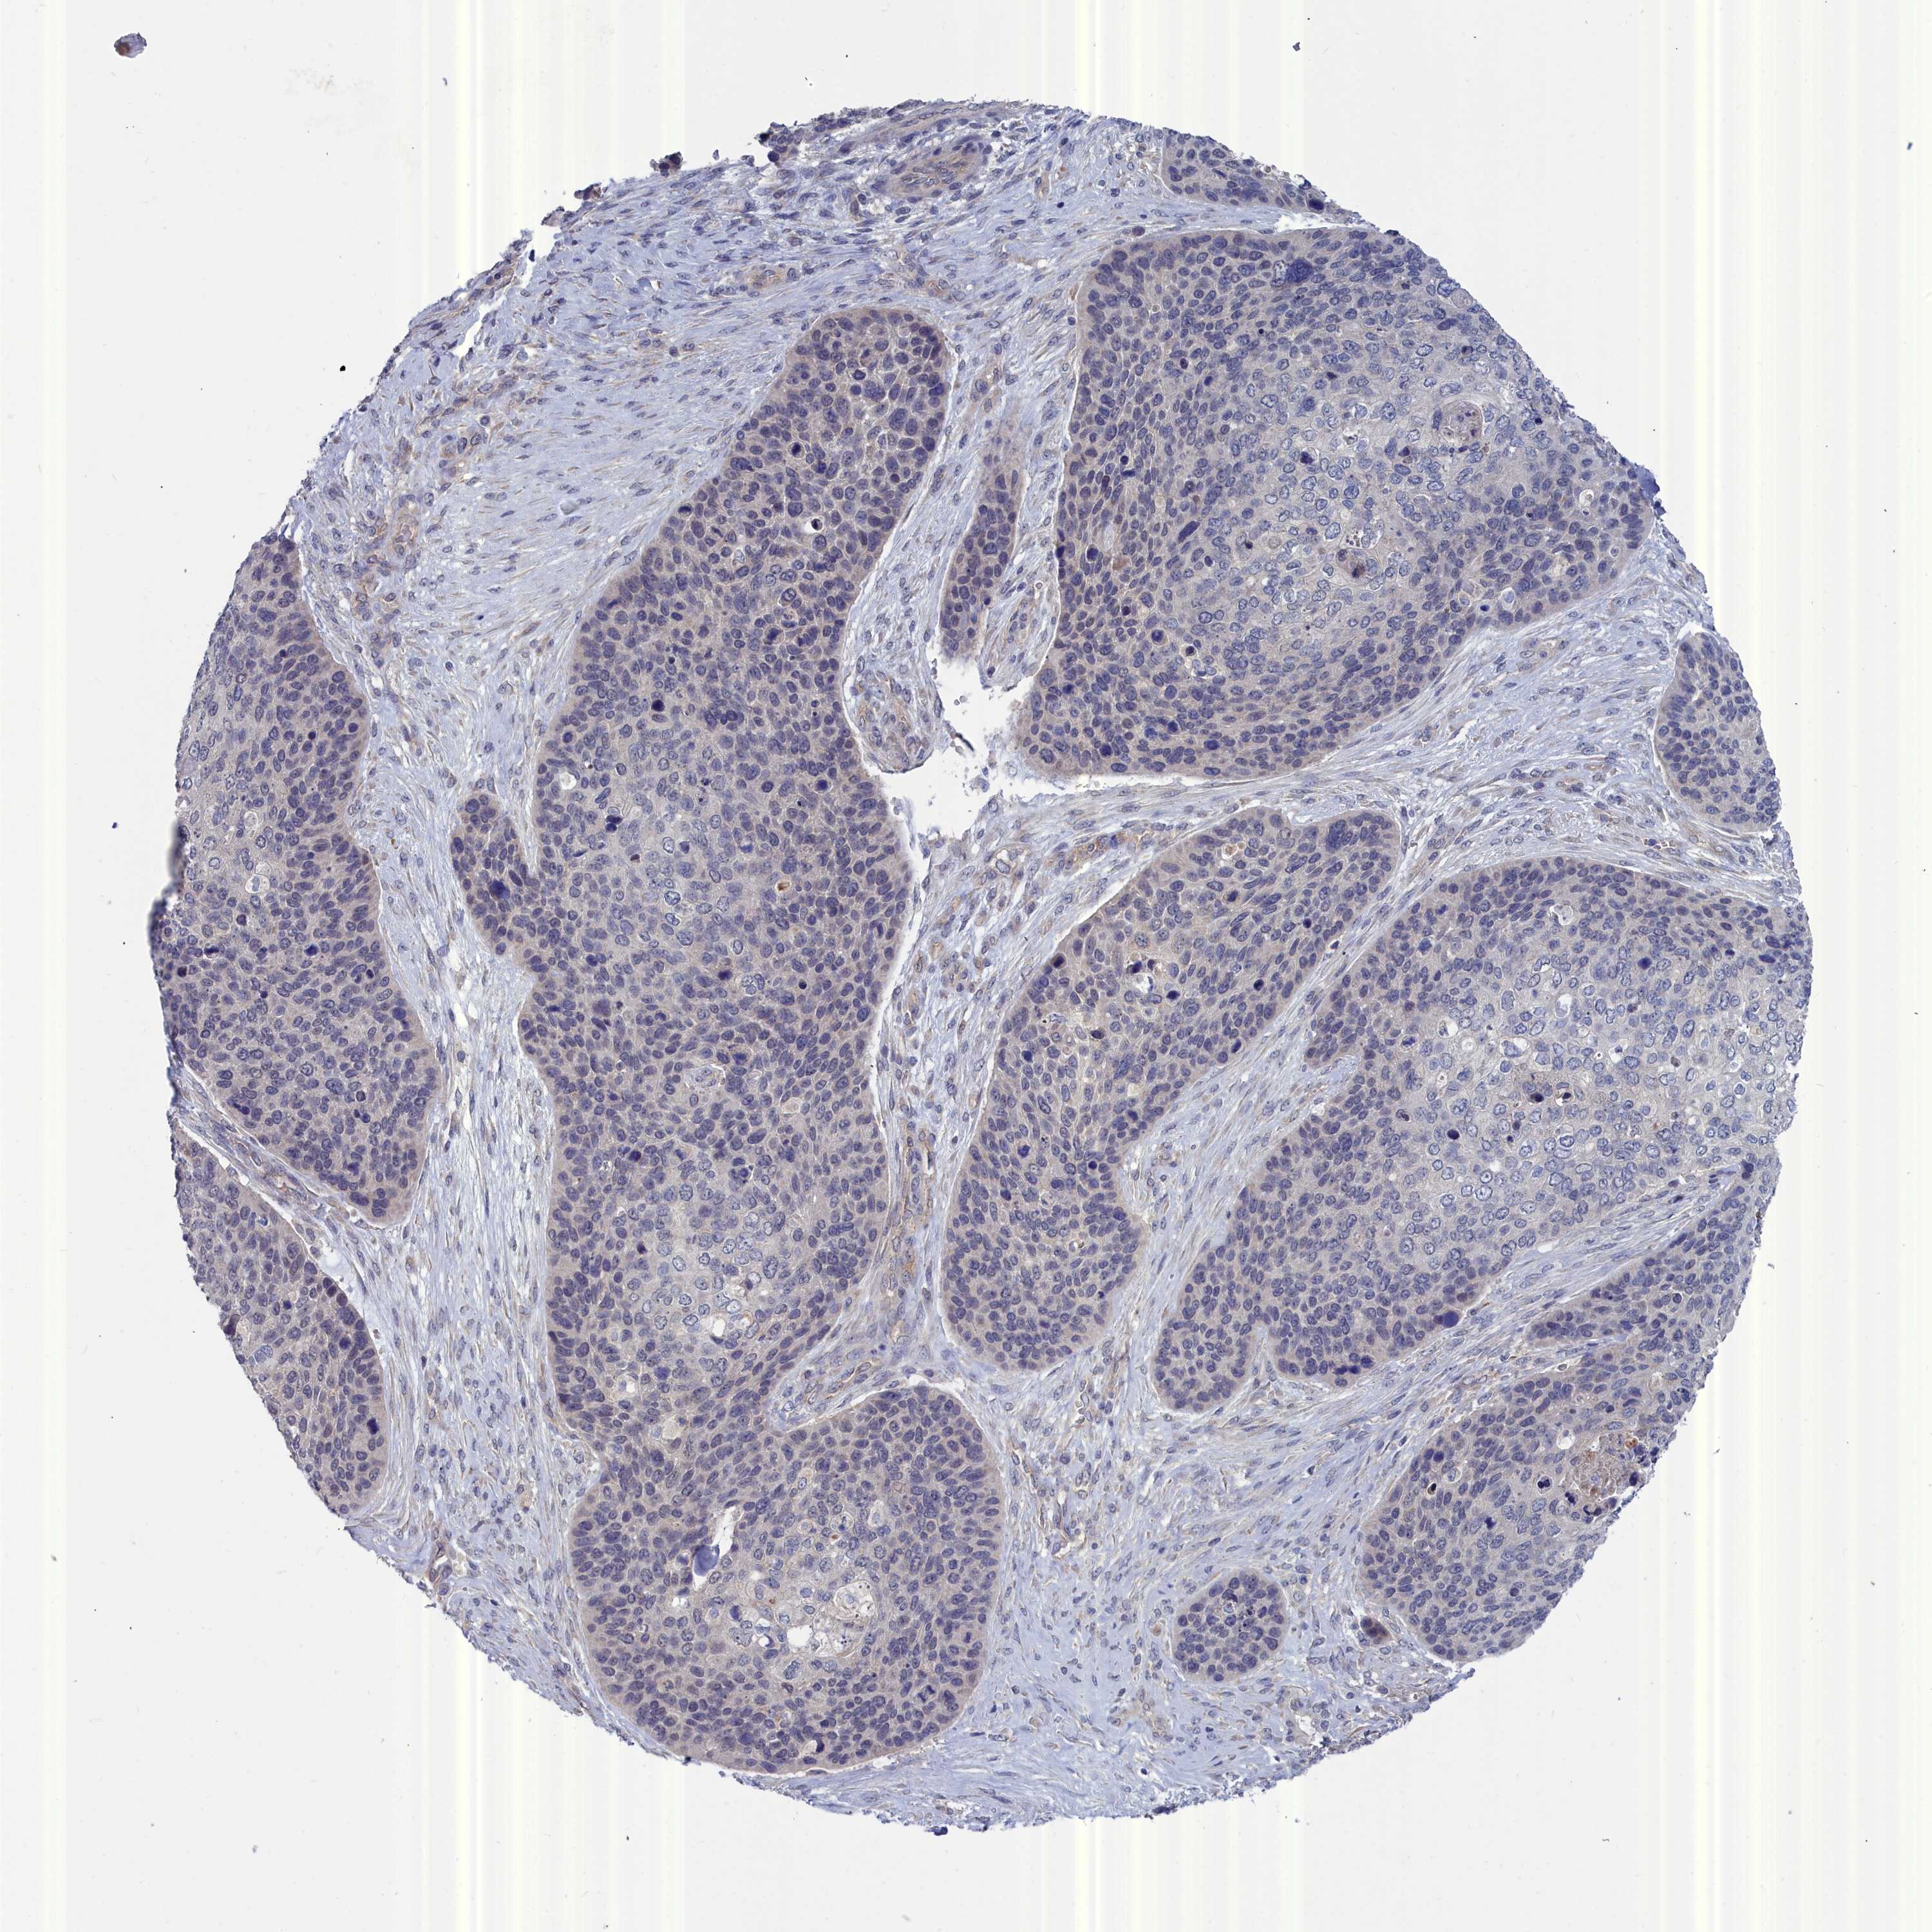

SKIN CANCER - Protein expressioni

A mouse-over function shows sample information and annotation data. Click on an image to view it in a full screen mode. Samples can be filtered based on level of antibody staining by selecting one or several of the following categories: high, medium, low and not detected. The assay and annotation is described here.

Each image is clickable and will lead to virtual microscopy that enables deeper exploration of all samples and also displays staining intensity scores, fraction scores and subcellular localization as well as patient and tissue information for each sample.

Antibody HPA000263

Staining

High

Medium

Low

Not detected

Intensity

Strong

Moderate

Weak

Negative

Quantity

>75%

75%-25%

<25%

None

Location

Nuclear

Cytoplasmic/membranous

Cytoplasmic/membranous,nuclear

Squamous cell carcinoma, NOS